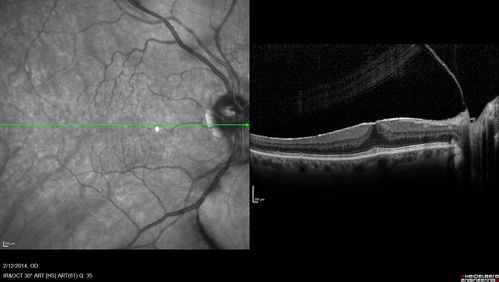

Vitreomacular Traction -> Macular Hole -> Aborted Macular hole

Progression of VMT in both eyes over time